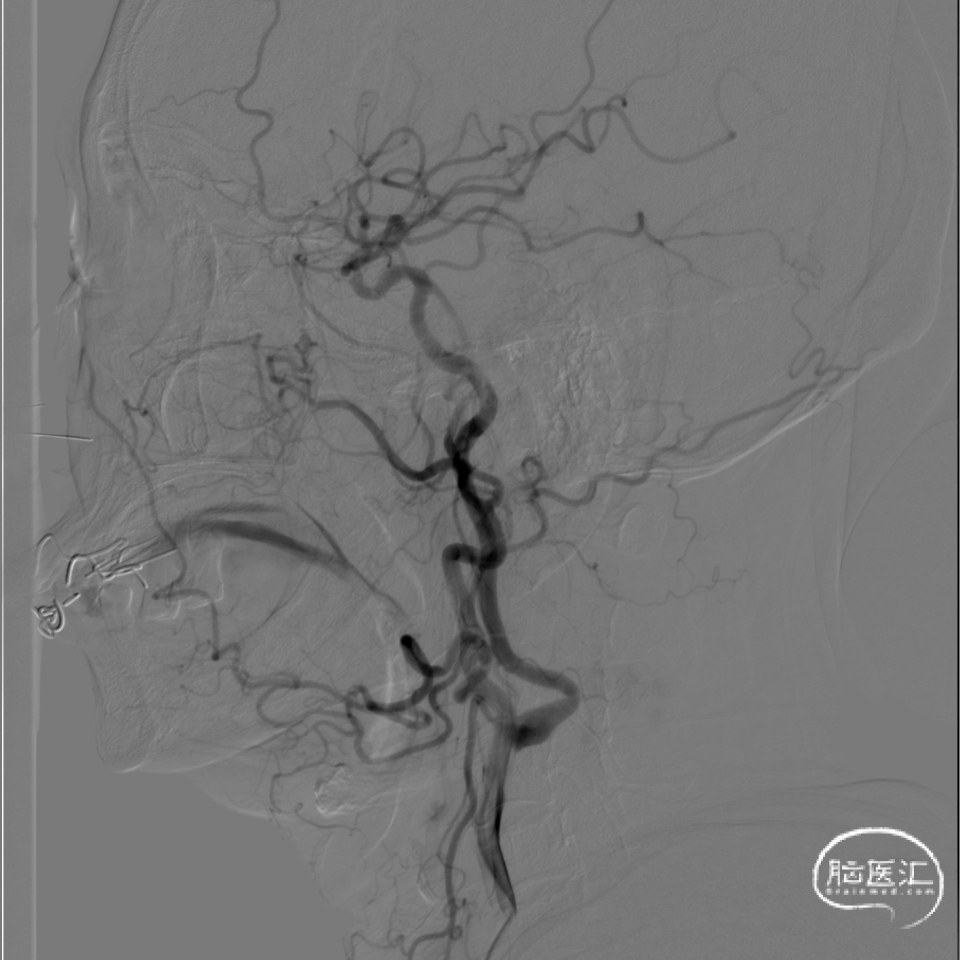

3、椎基底动脉系统:

右侧椎动脉优势型。

左侧椎动脉血管纤细,远端可见基底动脉浅淡显影。

右侧椎动脉优势型,远端汇入基底动脉。

基底动脉中段重度狭窄,狭窄率约80%,双侧大脑后动脉可见显影。

术前DSA影像:

右侧桡动脉穿刺置动脉鞘,泥鳅导丝配合6F 115cm Valent®颅内支撑导管内嵌行至右侧锁骨下动脉近右侧椎动脉起始段处,将导丝配合中间导管上行至椎动脉V3段,撤出泥鳅导丝,手推造影,显示:基底动脉中段可见重度狭窄,狭窄率约80%。